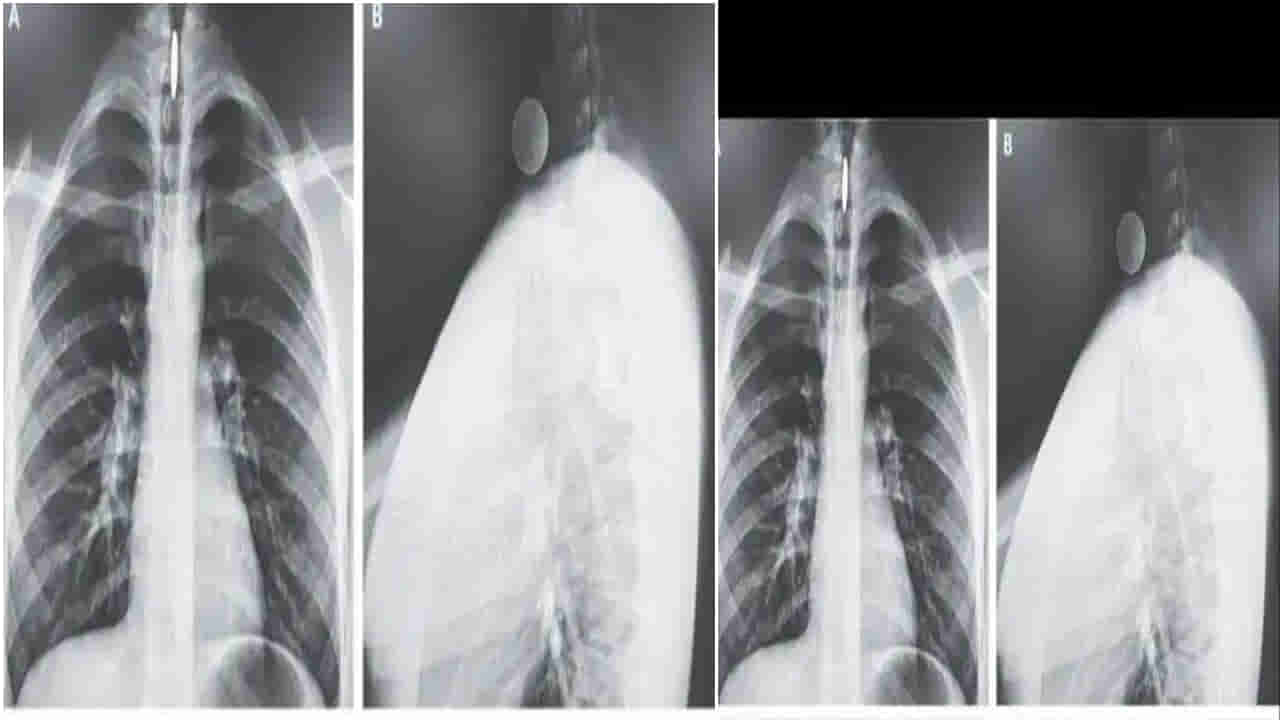

వివరాల్లోకెళ్తే.. న్యూ ఇంగ్లాండ్ జర్నల్ ఆఫ్ మెడిసిన్లో ప్రచురించిన నివేదిక ప్రకారం.. కాలిఫోర్నియాకు చెందిన 14 ఏళ్ల బాలుడు సరదాగా ఆడుకుంటూ ఓ నాణేన్ని మింగేశాడు. ఇక్కడ ఆశ్చర్యకరమైన విషయమేంటంటే.. ఎక్స్రే తీసిన డాక్టర్లు.. అది ఇరుక్కున్న ప్రదేశం చూసి దెబ్బకు షాక్ అయ్యారు. ఆ నాణెం అన్నవాహికలో కాకుండా స్వరపేటికలో ఇరుక్కుపోయింది. దీంతో అతడు తినేటప్పుడు, మాట్లాడేటప్పుడు గానీ ఎలాంటి ఇబ్బంది పడలేదు. కుటుంబసభ్యులు ఆ బాలుడిని ఆసుపత్రికి తీసుకురాగా.. అక్కడి డాక్టర్లు అతడికి ఎక్స్రే తీసి కాయిన్ ఎక్కడ ఇరుక్కుందో చూశారు. కెమెరా సాయంతో ఫోర్సెప్స్ ద్వారా ఆ నాణేన్ని జాగ్రత్తగా బయటకు తీశారు. ఆపరేషన్ అనంతరం బాలుడి ఆరోగ్యం కుదుటపడిందని.. ఎలాంటి ఇబ్బందులు లేకపోవడంతో అతడ్ని డిశ్చార్జ్ చేసి ఇంటికి పంపించామని డాక్టర్లు చెప్పారు.(Source)